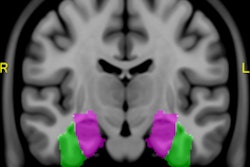

Attenuation correction has also proved to be a challenge for PET/MRI, which is seen as a possible breakthrough in oncology for its ability to simultaneously provide molecular, functional, and anatomical information. Patient motion, leading to misalignment of data between MRI and PET, has proved to be a particular concern, according to Dr. Harald Quick, director of the University of Duisburg's Erwin L. Hahn Institute for MR Imaging in Essen, Germany.

In addition, obesity and metal prostheses also can constrain MR field-of-view. Hip implants, for example, are known to create large-volume artifacts and signal voids in MR images that could affect diagnostic assessments of surrounding tissues, he explained.

Researchers are focusing on several improvements to address image accuracy. These include the use of continuous attenuation values for multiple tissue classes, detection of bone tissue, assignment of different attenuation correction values for lung tissue of differing density, motion correction measures, correction of truncated areas, and reducing metal artifacts.

"With PET/MRI, we currently see the implementation of bone tissue in the head region by using ultrashort echo time sequences, the addition of bones in the body by using atlas-based methods, the correction of truncation artifacts using new sequences that are able to extend the MR imaging field-of-view (HUGE), the correction of motion artifacts in thorax and liver imaging, and finally, the reduction of metal artifacts around implants using appropriate metal artifact reduction sequences," Quick stated.